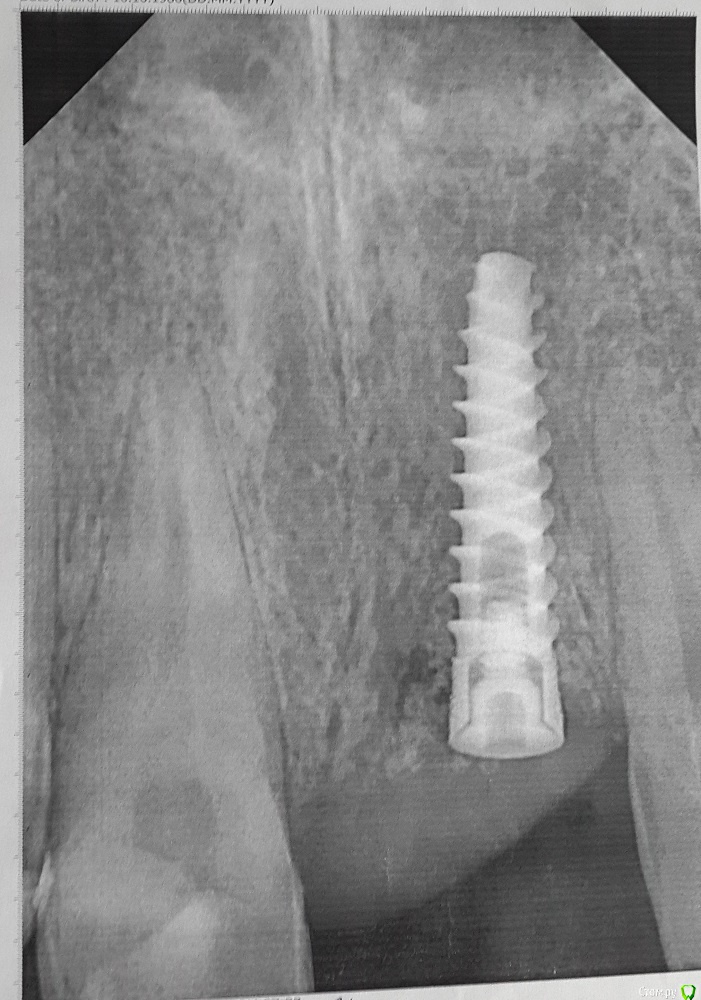

pekar Опубликовано 20 мая, 2016 Автор Поделиться Опубликовано 20 мая, 2016 Фото с "зубом" нет. Вот рг: Ссылка на комментарий

pekar Опубликовано 19 мая, 2016 Поделиться Опубликовано 19 мая, 2016 Здравствуйте. Поставили имплант (одномоментно с удалением больного зуба), а через 4 месяца формирователь, но десна ушла очень глубоко. Возможно ли это как то исправить? Изготовили зуб, мне он не понравился, очень длинный, бросается в глаза, хоть он и розового цвета в основании. Ссылка на комментарий

red_butler Опубликовано 23 мая, 2016 Поделиться Опубликовано 23 мая, 2016 Ситуацию можно улучшить с помощью пластики мягких тканей. 1 Ссылка на комментарий

Bier Опубликовано 23 мая, 2016 Поделиться Опубликовано 23 мая, 2016 можно улучшить, но коронку нужно выбросить. Нарастить десну, потом делать новую коронку 1 Ссылка на комментарий

Larnary Опубликовано 26 мая, 2016 Поделиться Опубликовано 26 мая, 2016 (изменено) Обращаться к хирургу. Он сделает пластику мягких тканей,а ортопед временной коронкой смоделирует десну и только потом уже постоянная коронка.Хирурга винить не буду,тк неизвестны условия до операции. Тут скорее несогласованность работы хирурга и ортопеда. Изменено 26 мая, 2016 пользователем Larnary Ссылка на комментарий